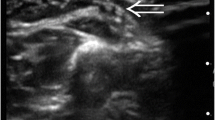

Position 3—This position follows the basilic vein with the probe position on the medial side of arm in the bicipital humeral groove. Assess the basilic vein in relation to the ulnar nerve and brachial bundle with the brachial veins, artery, and median nerve. Assess basilic vein along the bicep groove for compressibility, thrombosis, diameter, and distance from the skin (Figs. 2.4, 2.5. This mid-upper arm position is a common location for PICC insertion stabilized by the surrounding bicep, brachialis, and coracobrachialis muscle group.

Position 1—Starting at the mid neck examining the internal jugular vessels and the carotid artery using a transverse view of the vessels. This position assesses the internal jugular vein (IJV) and carotid artery. Assess for compressibility, size, and shape (Figs. 2.10 and 2.11). Where possible and safe to do so for your patient, pressure should be applied to the veins to assess for compressibility and to check for patency and the presence of a thrombosis. The development of a thrombosis is a process, and in the early stages, the thrombus is still compressible (though the vessel is not likely to fully compress). At this stage it may also appear black and, like a normal vessel, only at the later stages does it start to take on a more solid form and then becomes more echogenic and the vein non-compressible. Any suspicion of a thrombus should be referred to the radiology and or vascular team for further investigation including Doppler ultrasound assessment.